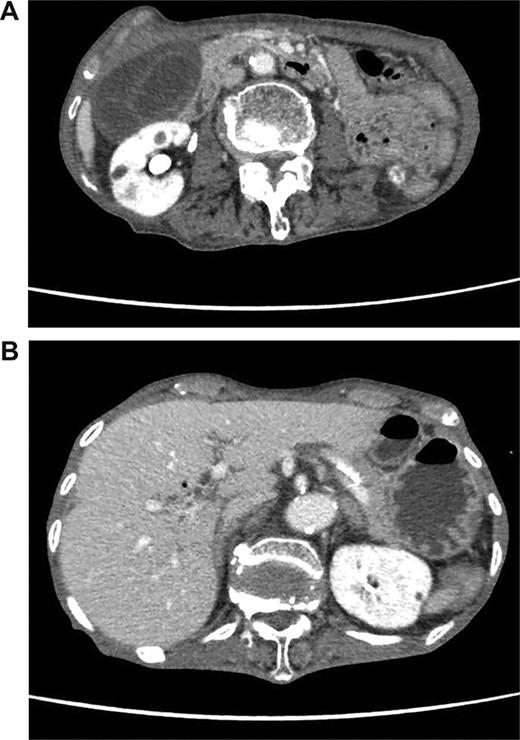

On admission, her vital signs were normal. Her medical history included dermatomyositis, hypertension and osteoporosis. She had a white blood cell count of 10.6 × 103/μL, hemoglobin of 8.2 g/dL and lactic acid of 0.8 mmoL/L. A physical examination demonstrated strong tenderness in her right upper quadrant abdomen. Ultrasonogramphy (US) showed diffuse wall thickening of her gallbladder without cholecystolithiasis. US also revealed small mobile echogenic foci moving inside the portal venous branches (Fig. 1). The hyperechogenic foci were seen in the middle segment and right anterior segment of the liver. Contrast-enhanced computed tomography (CT) showed a diffusely thickened wall of the gallbladder with poor enhancement, suggesting acute necrotizing cholecystitis (Fig. 2). Tiny bubbles were seen in the intrahepatic portal venous branches (segment 4 and segment 5), but there was no evidence of bowel ischemia. She was then diagnosed with necrotic cholecystitis and immediately underwent emergency operation.

(A) Ultrasonography shows distention and wall thickening of the gallbladder. (B) Ultrasonography shows small mobile echogenic foci and hyperechogenic linear structures in the middle segment and right anterior segment of the liver.